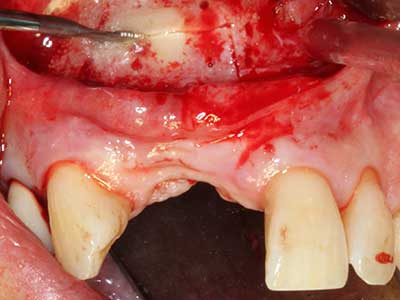

Bone tissue is not simply a mineral structure but also contains a substantial proportion of collagen fibres. This means it not only has good compressive strength but also a degree of flexibility, which can be taken advantage of when performing bone augmentations. In the classical expansion procedure using bone splitting, the atrophied alveolar ridge is split longitudinally and carefully expanded after reaching an adequate osteotomy depth (Fig. 13-16), ideally without substantial removal of the periosteum (Brugnami, Caiazzo et al. 2014, Stricker, Fleiner et al. 2014). Screw and plate systems with increasing expansion distance have proven effective in separating the two bone lamellae while remaining below the fracture threshold. In general, residual bone widths of at least 3–4 mm are required (Chiapasco, Zaniboni et al. 2006) to guarantee adequate flexibility and sufficient bone coverage of the future implants. If necessary, a vertical relief osteotomy on one or both sides can improve flexibility. A combination with additional augmentation techniques, particularly on the buccal side, has been described as an alternative to the classical technique.

The splitting procedure is particularly atraumatic and there is no significant loss of dimension when using piezosaws, and there are no significant differences between implants in split jaws and implants in an alveolar ridge without a bone deficit (Chiapasco, Zaniboni et al. 2006, Danza, Guidi et al. 2009). However, sufficient continuous irrigation is essential, particularly with locally restricted and deep splitting to prevent thermal stress in the apical osteotomy regions.